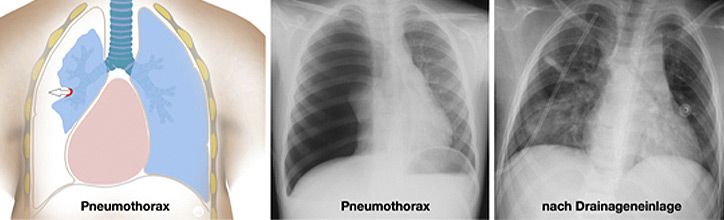

Thoraxtraumen betreffen sowohl den Weichteilmantel, das knöcherne Skelett (Rippen, Wirbelsäule) als auch die intrathorakalen Organe (V.a. Lunge, aber auch Speiseröhre, das Zwerchfell, die großen Gefäße und das Herz). Die Verletzungen können durch Verbrennungen entstehen, durch Verschlucken von Fremdkörpern oder giftiger Flüssigkeiten sowie durch stumpfe oder seltener spitze Gewalt. Beim eigentlichen Thoraxtrauma sind die inneren Organe betroffen, wobei es sich um ein schweres Krankheitsbild handelt, welches im Kindesalter dennoch in der Regel konservativ zu therapieren ist.

Grundlegender Unterschied beim Kind verglichen mit dem Erwachsenen, ist die geringere Körpergröße und Masse sowie die hohe Plastizität der knorpeligen Rippen. Diese frakturieren (brechen) beim stumpfen Thoraxtrauma in der Regel nicht, leiten aber die Kraft der Gewalteinwirkung vielmehr auf die darunter liegenden Strukturen fort. Folge können Gewebezerreissungen der Lungenstrukturen sein mit der Folge von Blutungen, Ödembildung, Pneumo- oder Hämatothorax (Abbildung)